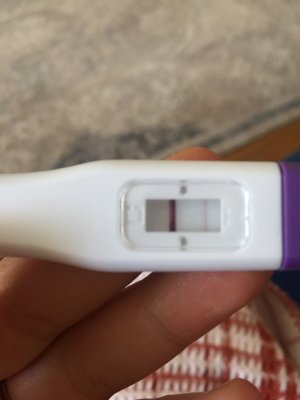

Merhaba kızlar ben reglme 2 gün kala erken gebelik testi yaptım silik çizgi çıktı snra emin olmak için bir tane daha yaptım oda silik cıktı bu gun regl gunum olmadım gittim normal gecelik testi yaptım onda da çok silik çizgi cıktı sizdn fikir almak istiyorum sizce var mı testleri buraya koycam karartma yaptım

Erken gebelik testi